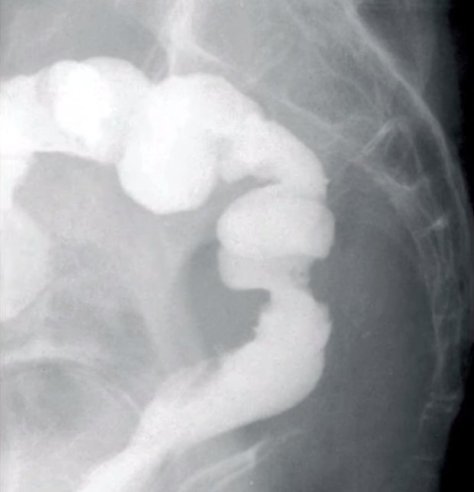

자스민카 벨코브스카라는 마케도니아 여성은 상피성 암으로 병원에 입원한 상태였다. 이를 제거하기 위해 그녀는 수술을 받았다.

이튿 날 그녀는 깜짝 놀랄 만한 문제에 직면했다. 바로 대장과 자신의 성.기가 연결되어 방귀가 중요부위에서 나왔던 것.

지역 TV와의 인터뷰에서 그녀는 “수술을 마치고 의사들이 방귀가 나오면 말해달라고 했어요. 그래서 방귀를 마침 뀌었는데, 그것이 제 중요부위에서 나왔습니다.”라고 밝혔다.

심지어 그녀는 수술일이었던 9월 8일, 의료진들이 암 덩어리를 제거하지 못하고 이상한 수술을 진행했다고 주장했다.